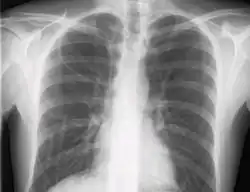

The line is then inserted using the Seldinger technique: a blunt guidewire is passed through the needle, then the needle is removed. A dilating device may be passed over the guidewire to expand the tract. Finally, the central line itself is then passed over the guidewire, and the wire is then removed. All the lumens of the line are aspirated (to ensure that they are all positioned inside the vein) and flushed with either saline or heparin.[1] A chest X-ray may be performed afterwards to confirm that the line is positioned inside the superior vena cava and no pneumothorax was caused inadvertently. On anteroposterior X-rays, a catheter tip between 55 and 29 mm below the level of the carina is regarded as acceptable placement.[10] Electromagnetic tracking can be used to verify tip placement and provide guidance during insertion, obviating the need for the X-ray afterwards.

Chest x-ray with catheter in the right subclavian vein

The outline of superior vena cava on a chest X-ray is labeled at left.

During subclavian vein central line placement, the catheter can be accidentally pushed into the internal jugular vein on the same side instead of the superior vena cava. A chest x-ray is performed after insertion to rule out this possibility.[32] The tip of the catheter can also be misdirected into the contralateral (opposite side) subclavian vein in the neck, rather than into the superior vena cava.